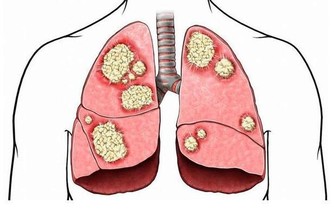

此外,呼吸是每個人必備的,而空氣難免會摻雜著一些微小的顆粒或者是細菌,這些東西隨著空氣,一同被吸進身體裡面。經過長時間的累積,量就會不斷增多。如此一來,身體的毒素就會變多,從而個身體帶來更多的傷害。